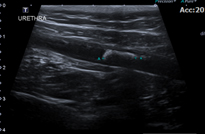

결석은 신장, 요관, 방광, 요도 등 비뇨기 중 어디에도 생성될 수 있습니다. 결석이 비뇨기 폐색을 유발할 경우 아이가 갑자기 뇨를 보지 못하고, 급성 신부전이 발생할 수 있어 응급 수술을 필요로 할 수 있으며, 아이에게 지속적인 불편감을 유발하여 혈뇨, 잔뇨감 등 다양한 임상증상을 나타낼 수 있습니다. 폐색이 유발된 부분, 증상, 재발 여부에 따라 SUB (인공요관우회술) 및 요도를 넓혀주는 수술 등이 필요할 수 있습니다. 본원에서는 내과 및 영상의학과와의 협진과 다수의 비뇨기계 수술 경력의 외과 수의사를 통해 아이에게 필요한 수술법으로 진행하고 있으며, 내과 전담 수의사를 통해 장기적으로 재발 관리 및 모니터링을 지속하고 있습니다.